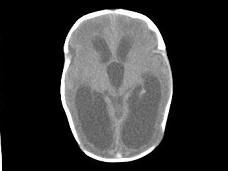

问题 1岁,女,头颅呈球状,颅骨透光试验阳性,请结合CT图像选择最可能诊断 ( )

选项 A、先天性脑积水 B、外部性脑积水 C、慢性双侧性巨大硬膜下血肿 D、水瘤 E、脑严重缺血

答案 A